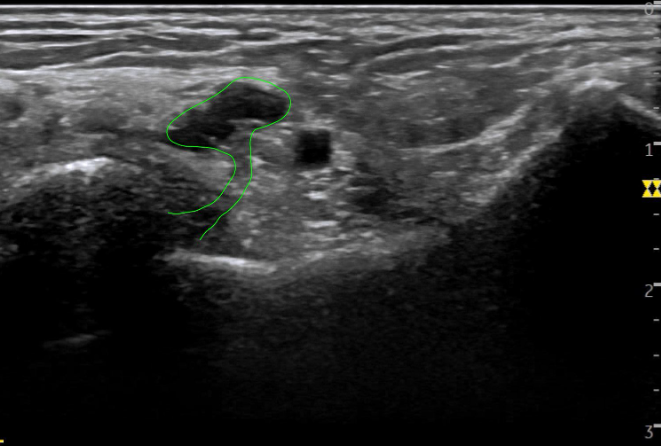

정상 경혈의 초음파 영상 이 부분은 경혈 초음파상 발목 터널 안쪽에 후경골신경의 분지와 후경골동맥, 정맥이 보여야 하는데

환자분의 수천혈 초음파 해당 환자분은 까만 물혹(빨간 화살표)이 보입니다.

경혈 초음파로 살펴보니 거골하관절로 연결된 것이 보입니다. 예전에도 관절염으로 물이 차서 결절종을 제거했던 적이 있으셨다고요. ## 이렇게 딱딱한 물혹이 터널 안에서공간을 차지하면서 발바닥신경을 압박하고 있는데지압한다고 꾹꾹 눌러대니증상이 악화되는 것은 당연하겠죠? 더군다나 평발로 발의 아치가 무너져있는데 오래 서있으니까 도수치료, 체외충격파로도 회복하기 어려웠을 겁니다. > 초음파 유도하 도침술 발목 터널의 압력을 빠르게 해결해주는 도침 치료를 시행했습니다. 실시간 초음파로 도침을 확인하면서 신경과 혈관을 피해서 정확하게 시술합니다.